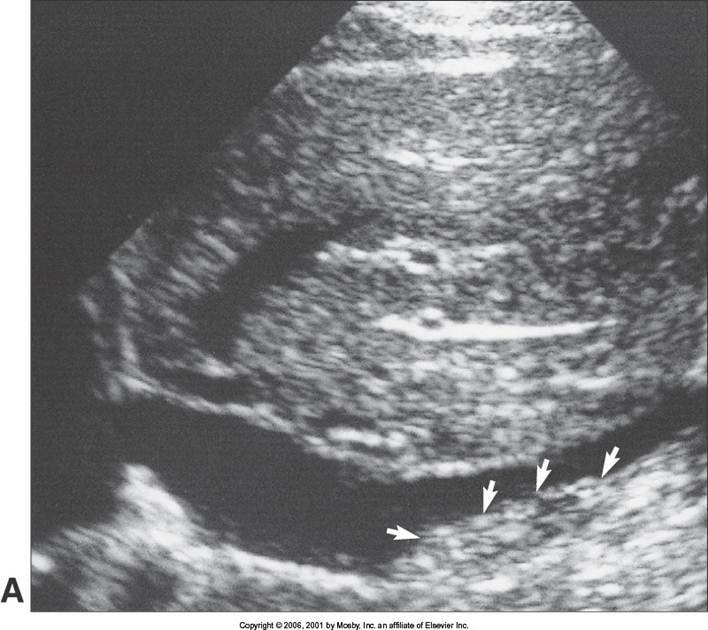

Aortic Dissection